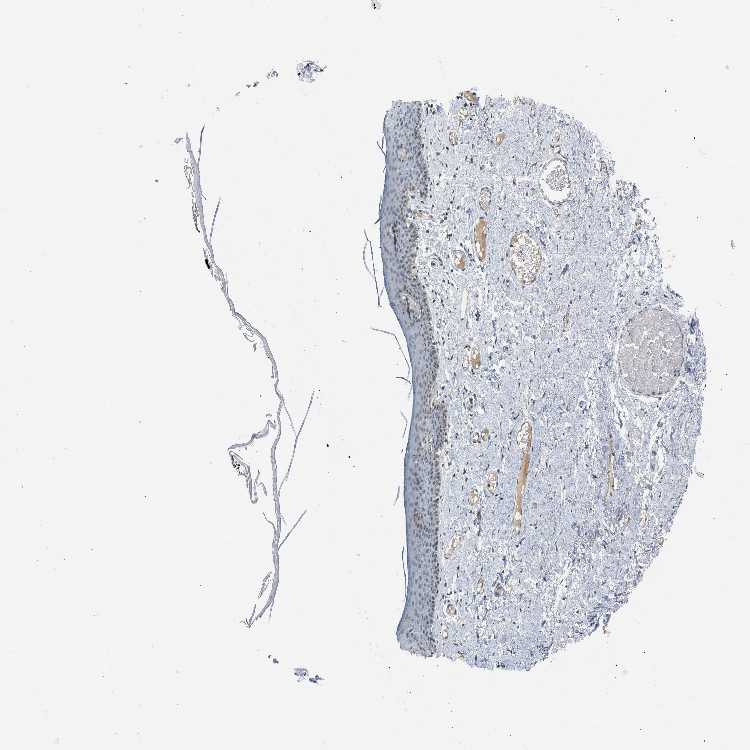

SKIN 2 - Antibody stainingi

Antibody staining in the annotated cell types in the current human tissue is reported as not detected, low, medium, or high, based on conventional immunohistochemistry profiling in selected tissues. This score is based on the combination of the staining intensity and fraction of stained cells.

Each image is clickable and will lead to virtual microscopy that enables deeper exploration of all samples and also displays staining intensity scores, fraction scores and subcellular localization as well as patient and tissue information for each sample.

Antibody HPA001757

Epidermal cells Not detected